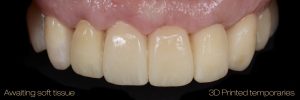

Second set of provisional restorations printed with GC Temp PRINT (medium shade) using the Asiga Max UV 3D printer. Fig. 13

Completed provisional crowns, implant retained crowns and bridge, characterized with OPTIGLAZE color (GC) – Dental technician: Brad Groblar, Oral Dynamics, New Zealand. Fig. 14

Completed provisionals fitted onto the printed models to allow the refinement of the contact points and occlusal contacts. Fig. 15 (i, ii)